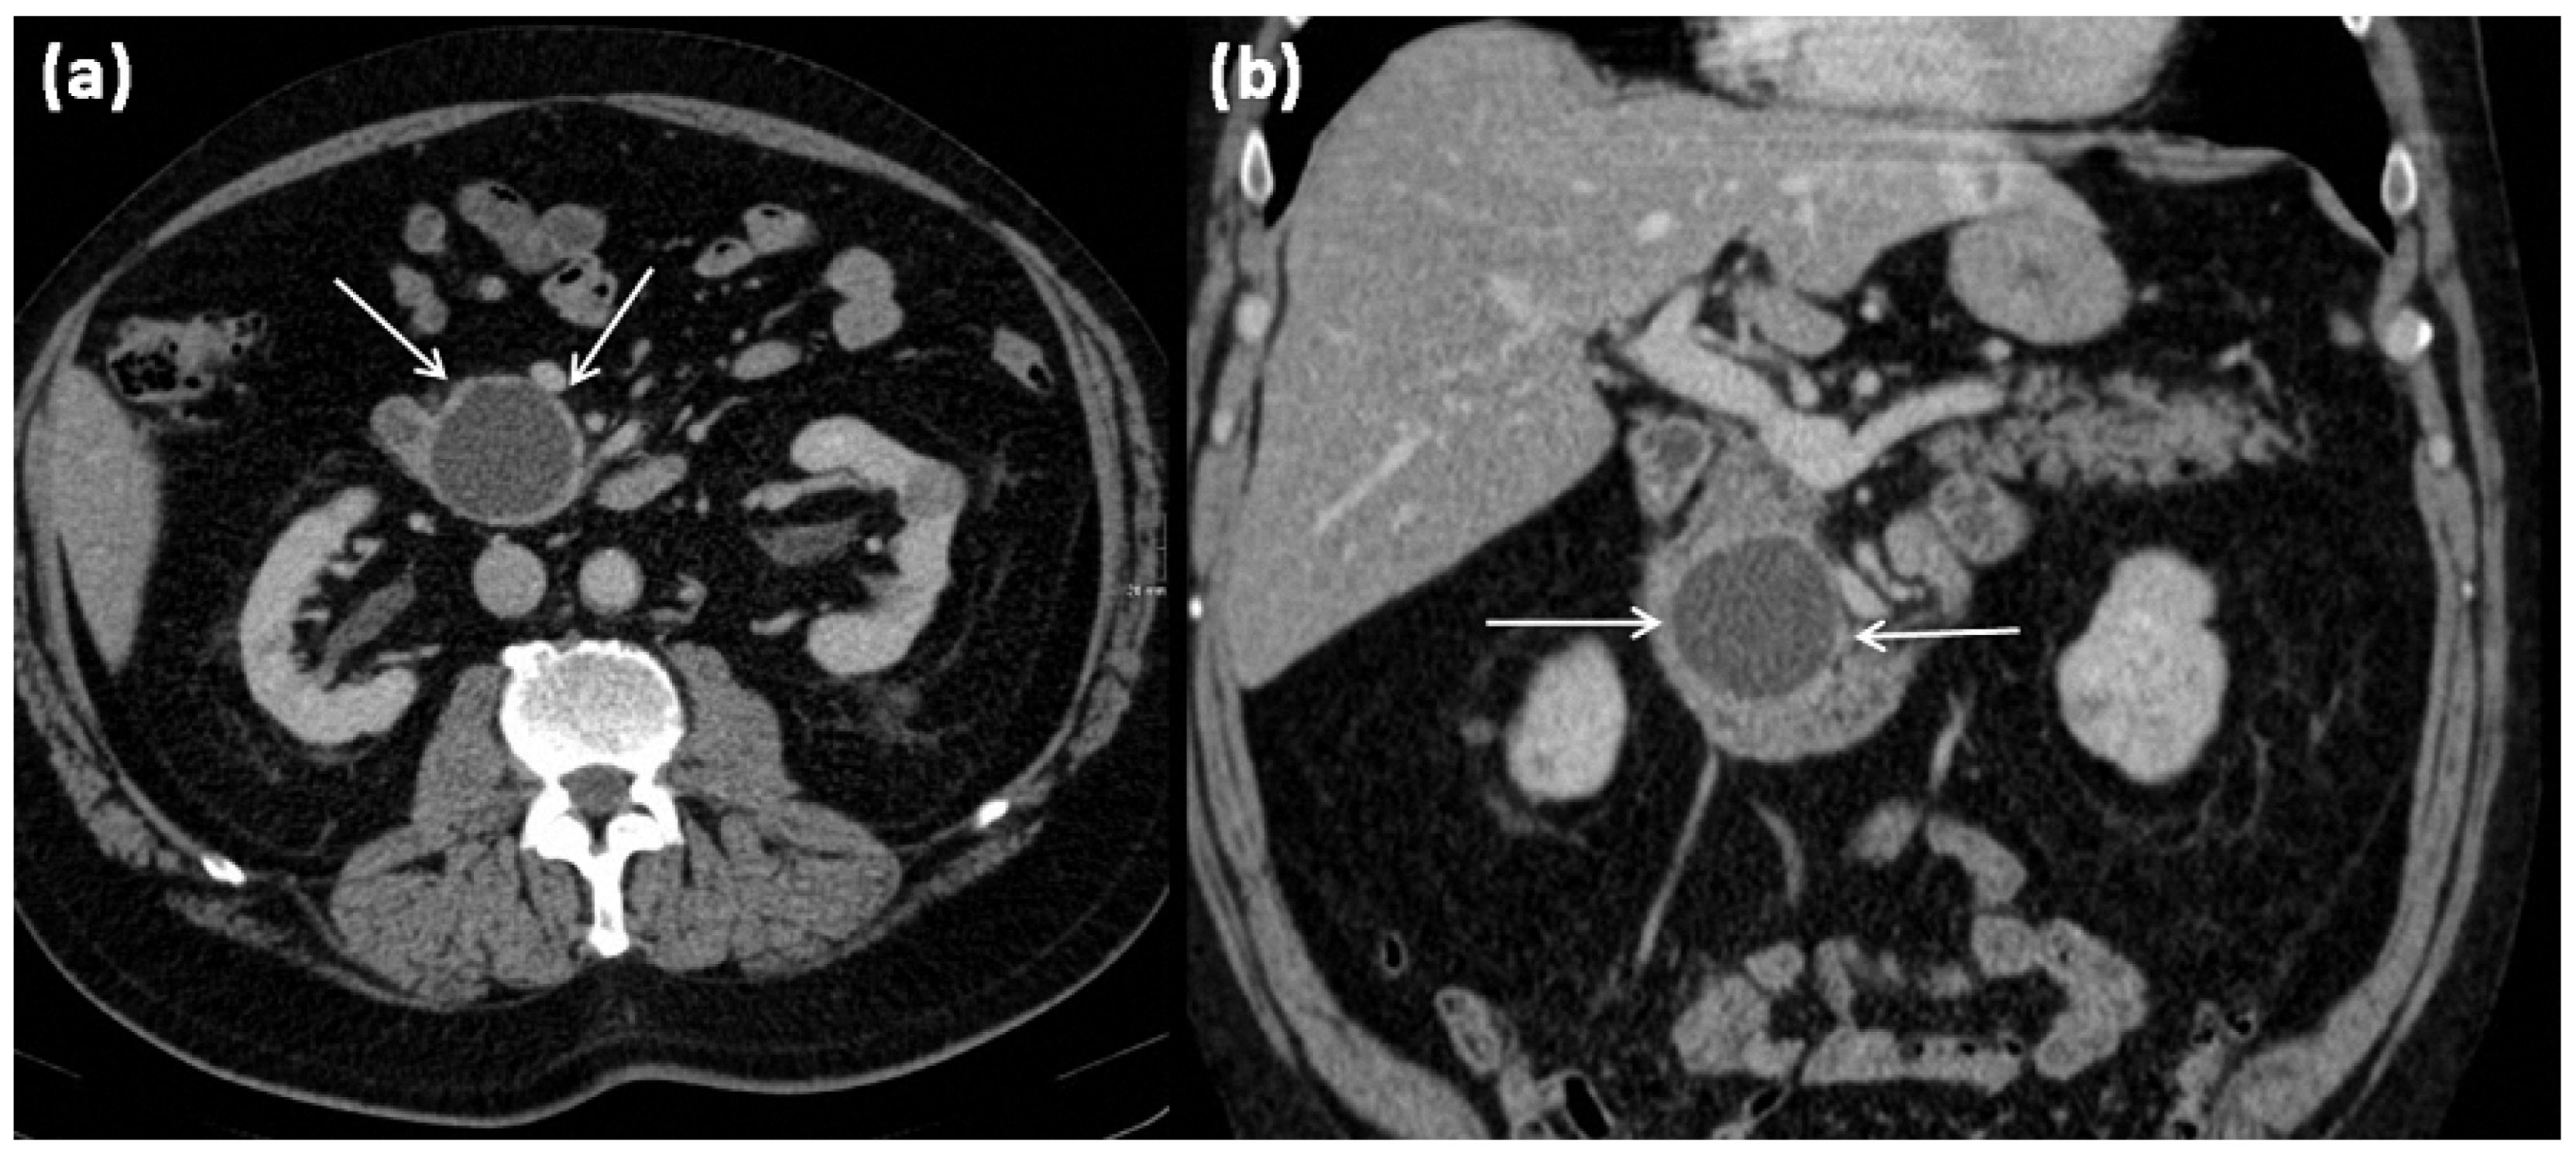

Figure 19.

MRI of a 79-year-old female patient with axial T1w (a) after gadolinium-based contrast administration, T2w, and (b) magnetic resonance cholangiopancreaticography (MRCP) (c). A merging and communicating multicystic formation is seen at the head of the pancreas, with the single cystic parts showing marked differences in size. Septa show mild contrast enhancement. In T2w a homogenous hyperintense signal is present. The tumor is marked with arrows in all sequences.